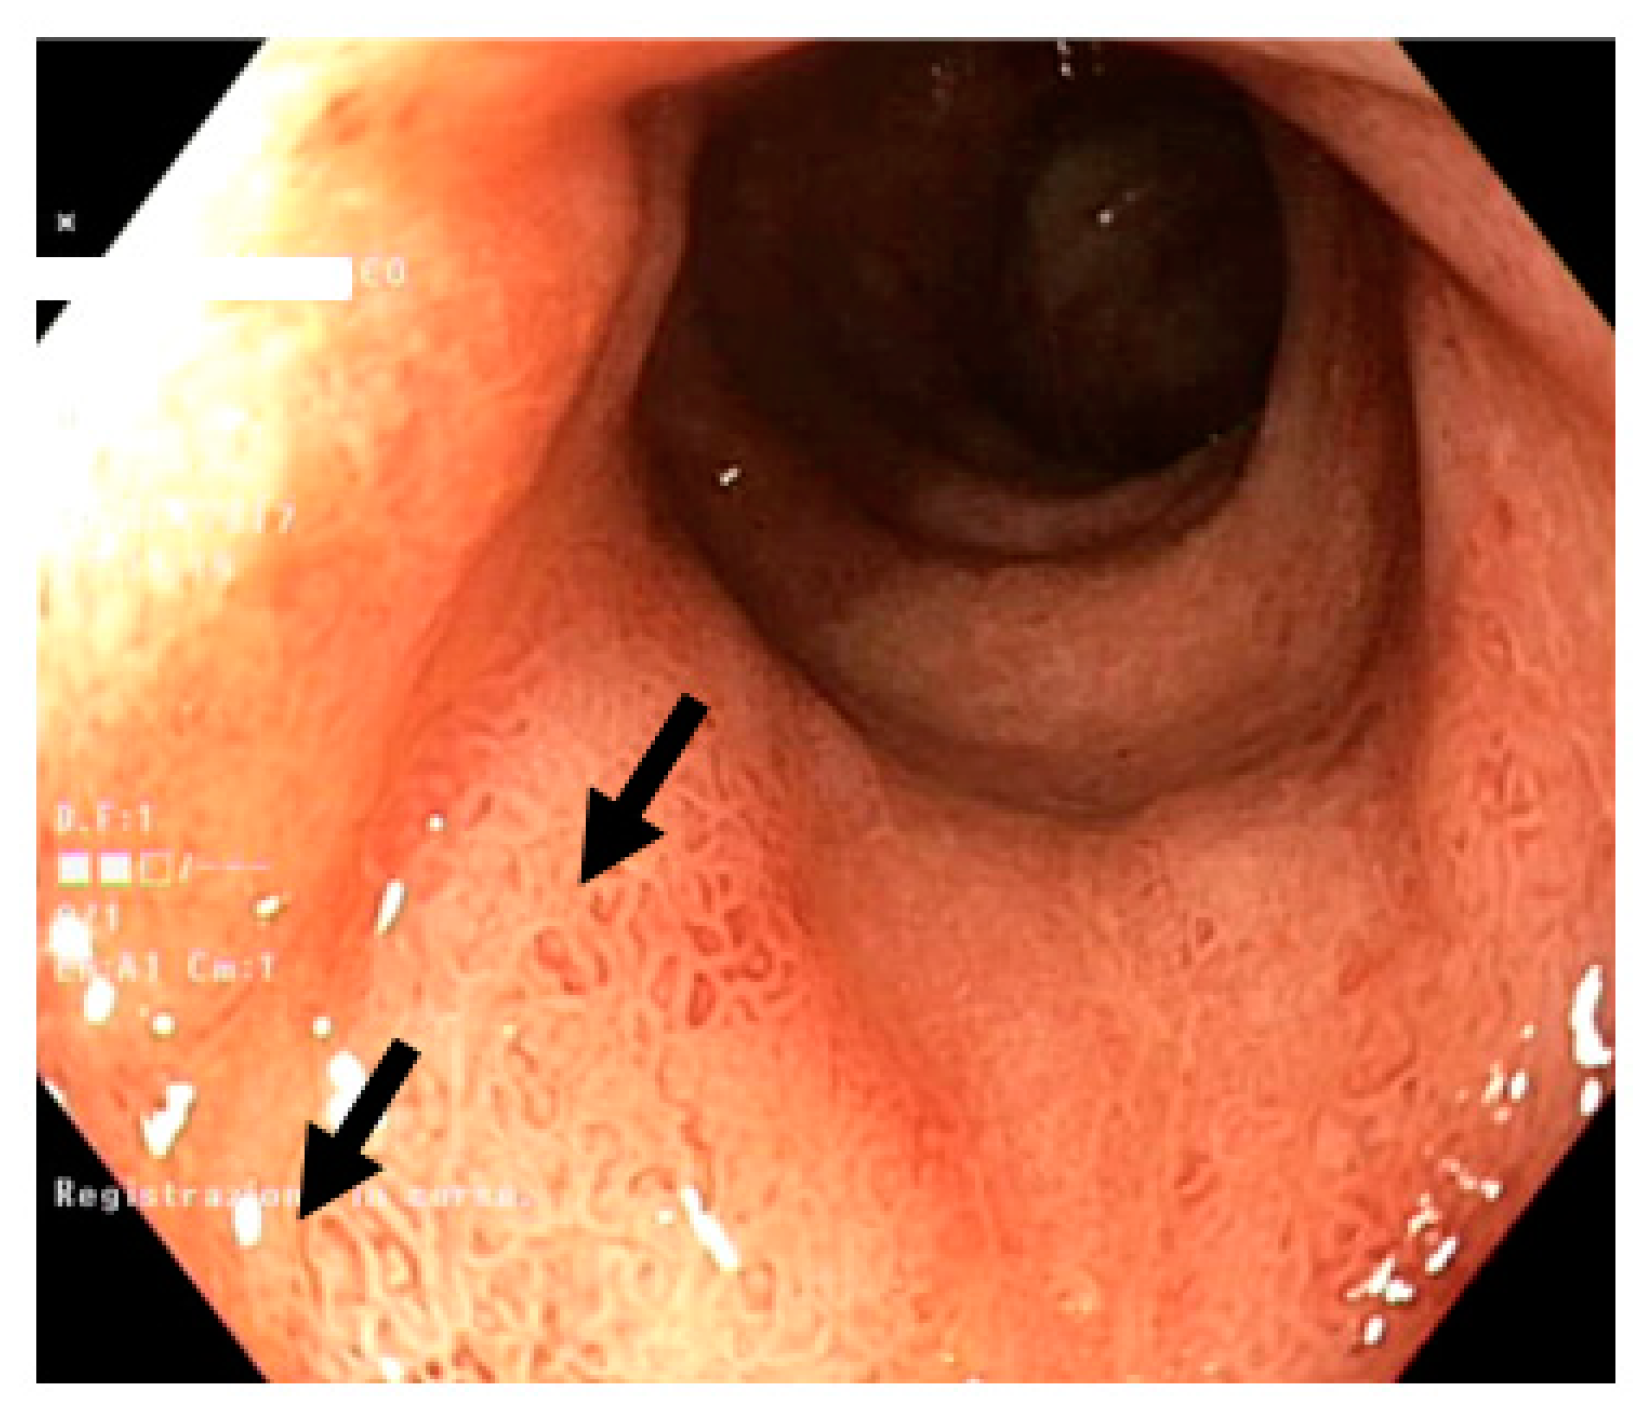

2.2. EMES

- erythema (0: absent, 1: mild, 2: moderate, 3: severe)

- submucosal vascular pattern (0: normal, 1: reduction, 2: disappearance)

- erosions (0: absent, 1: from 1 to 5 lesions, 2: from 6 to 10, 3: more than 10)

- ulcers (0: absent, 1: from 1 to 5 lesions, 2: from 6 to 10, 3: more than 10).